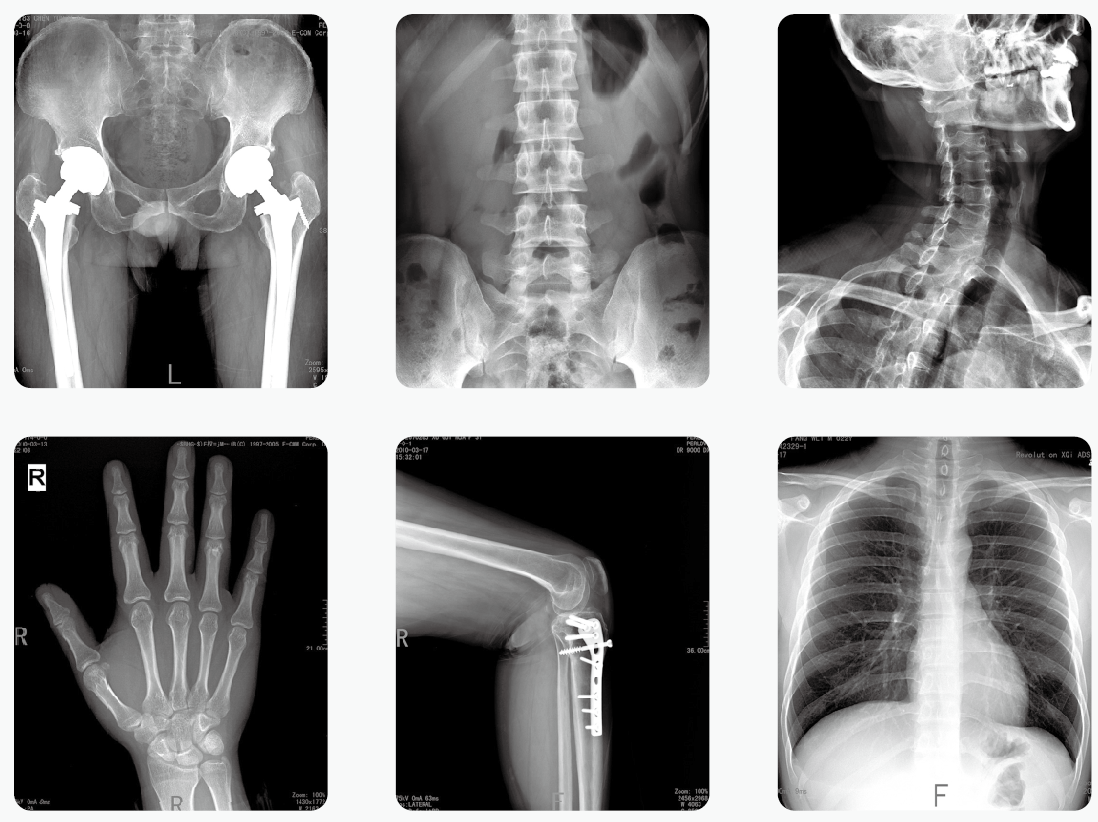

CT、DR等放射性醫(yī)學檢查會危害健康的說法一直存在,這讓很多有所耳聞但不明真相的群眾對這類檢查很抵觸。事實上,放射性的檢查的確會有輻射,但是作為必要的醫(yī)療手段,醫(yī)療器械的輻射劑量是固定的,且遵循檢查原則偶爾進行一兩次這樣的檢查并不會對健康造成顯著影響。

放射性醫(yī)學檢查——DR

做一次CT,致癌的幾率有多大?

從動物實驗來看,除非暴露在長時間、大劑量的照射,否則,一般出現(xiàn)癌變、發(fā)生骨髓抑制的概率很低很低。

那怎么解釋居里夫人死于再生障礙性貧血(骨髓抑制)呢?

那是因為她整天跟放射性物質(zhì)打交道,長期、大量地接觸放射性物質(zhì),相當于時時刻刻在照CT。

其實CT是不會使人體產(chǎn)生癌癥的,有些人之所以會認為CT會導致癌癥,就是因為CT的輻射,實際上CT的輻射是非常小的,可以忽略不計。

做一次CTDR檢查對人體的致癌概率僅僅只有萬分之一,只要自己并不是經(jīng)常性的做這種檢查的話,就不會有致癌的可能性,即使是經(jīng)常做,醫(yī)生和護士也會給檢查者做好及時的防護工作,不會導致癌癥的產(chǎn)生。

人們之所以會如此害怕CT,就是因為大部分的人都以訛傳訛,使得有些人認為CT是一項非常麻煩,而且對身體有害處的檢查。如果說自己本身就有癌癥的話,做CT手術(shù)更是非常有必要的,只有通過CT的檢查,才能夠知道自己的癌細胞到底有沒有擴散,也能夠知道身體的各項機能到底是否正常。

其實人體的檢查項目是有很多的,每一種項目都有自己的獨有特色,也有一定的功效,如果說忽略哪一項檢查不做的話,可能其他器官的病變就不會被發(fā)現(xiàn),CTDR是一項比較重要的檢查項目,是應(yīng)該要做的。